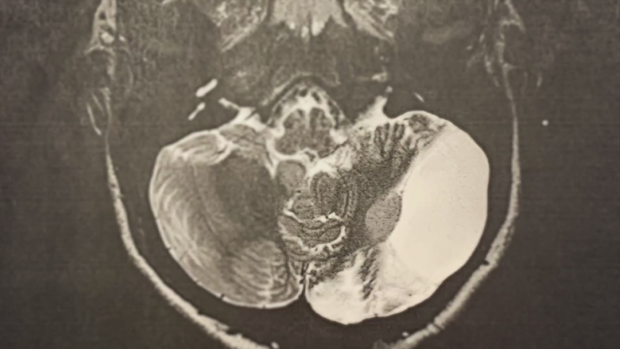

At just 5 years old, before starting kindergarten in 2016, Marin underwent surgery to remove a massive brain tumor.

Marin's tumor came back in 2024, requiring a second brain surgery.